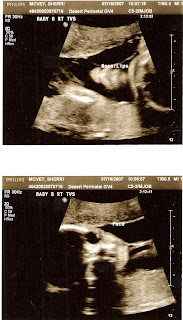

We had our doctors appointment on 7/16/07 and it was a long one. I did the one hour glucose test first, which wasn’t fun, but wasn’t too bad either. Then we had our ultrasound, which showed that the babies were laying across the bottom of my belly, stacked one on top of the other like a triple decker bus. All heads are laying on the right side and feet were to the left. No wonder I get kicked the most on the left side. Babies A and C are about 2 lbs. and baby B is about 1.5 lbs. and sandwiched in the middle. They are about 14 inches from head to toe. Then we went on to our first monitoring session for contractions. We will be monitoring weekly now for a month. There were no contractions the first session. My cervix has shortened by 1 centimeter and is now at 2 cm. The doctor said this was normal. We looked at the cerclage stitches and it seems to be the ONLY thing holding everything in. Wow, just amazing to see on the screen. Since it was a very lengthy ultrasound, we saw all the hearts, brains, kidneys and blood flow to both the placenta and through the umbilical cord. Very interesting to watch. The doctor thinks we’ll go into the low 30’s for delivery. I’m still shooting for 33 or 34 weeks, but Dr. Bohman will be happy if we make to 31 weeks. We will definitely need to go to Summerlin to deliver.